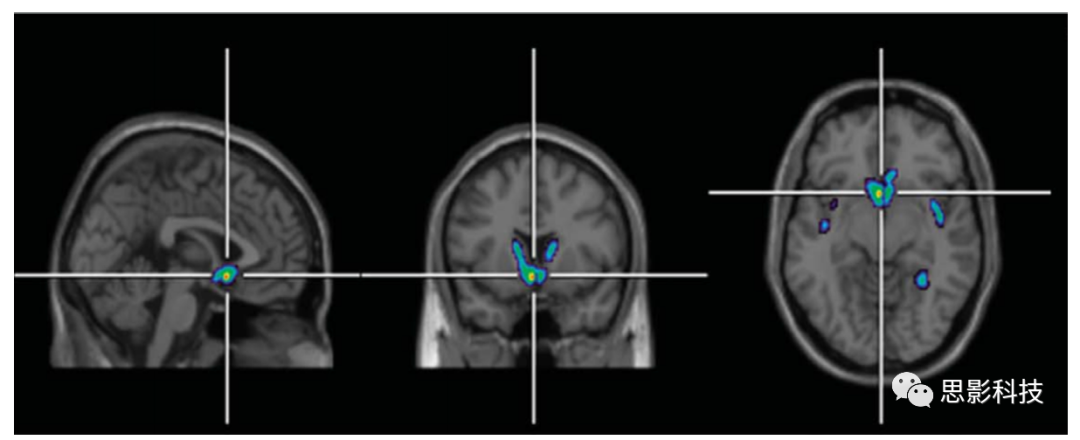

2 PET示例圖。

注:該圖來源于放射性示蹤劑11C-二丙諾啡的PET成像,用于說明OAn=15)和類風濕性關(guān)節(jié)炎(n=2)患者的阿片受體可用性。使用SPM8軟件進行回歸分析,以評估阿片受體可用性與近期McGill疼痛評分(作為過去一周慢性疼痛的衡量指標)之間的正相關(guān)關(guān)系。該圖顯示了這些患者的慢性疼痛與尾狀核、伏隔核和胼胝體下區(qū)阿片受體結(jié)合之間的正相關(guān)關(guān)系。突出顯示的區(qū)域表示重要區(qū)域。

縮寫:PET,正電子發(fā)射斷層掃描;OA,骨關(guān)節(jié)炎